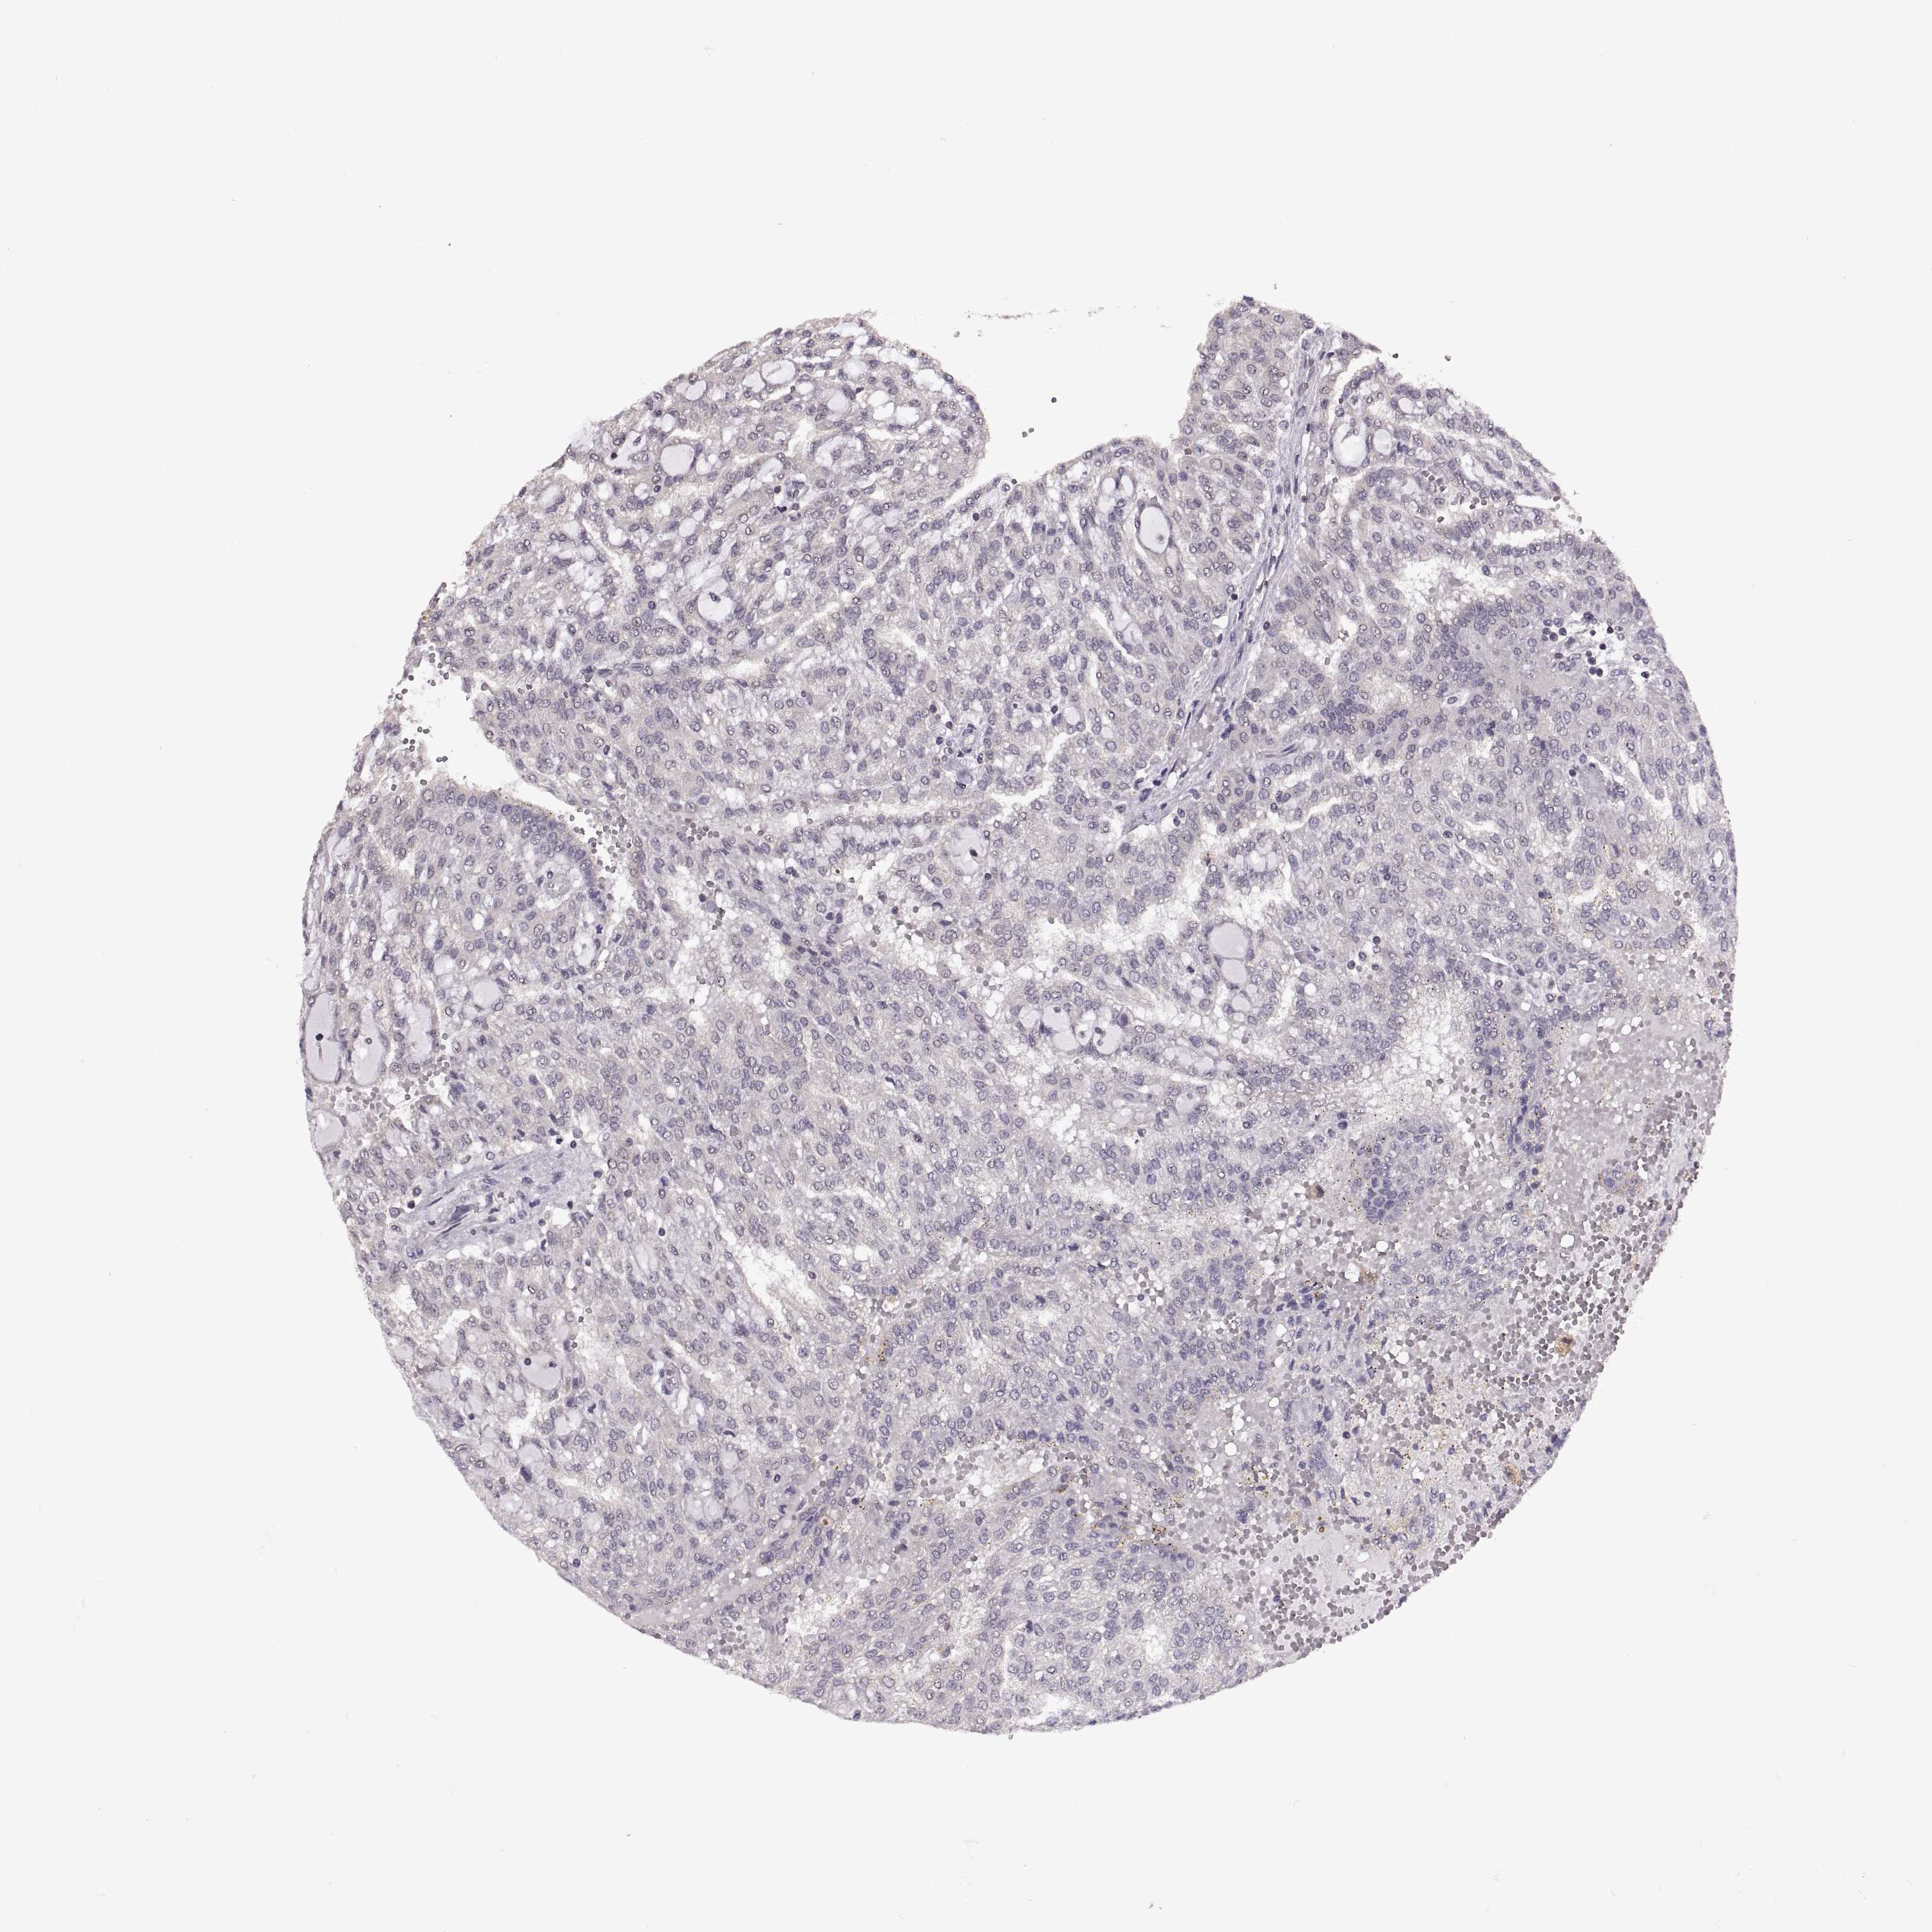

Renal cancer

Kidney renal clear cell carcinoma

KIDNEY RENAL CLEAR CELL CARCINOMA (TCGA) - Interactive survival scatter ploti

INTS3 is not prognostic in Kidney Renal Clear Cell Carcinoma (TCGA)

: 9.31

Average pTPM 9.4

Number of samples 521